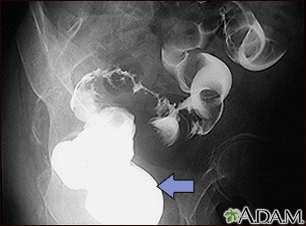

BACK TOTOP Browse A-ZSearchBrowse A-ZABCDEFGHIJKLMNOPQRSTUVWXYZ0-9 Sigmoid colon cancer - x-rayBackSigmoid colon cancer - x-rayA barium enema in a patient with cancer of the large bowel (sigmoid area). E-mail FormEmail ResultsName:Email address:Recipients Name:Recipients address:Message: Review Date: 4/1/2025 Reviewed By: Warren Brenner, MD, Oncologist, Lynn Cancer Institute, Boca Raton, FL. Review provided by VeriMed Healthcare Network. Also reviewed by David C. Dugdale, MD, Medical Director, Brenda Conaway, Editorial Director, and the A.D.A.M. Editorial team. The information provided herein should not be used during any medical emergency or for the diagnosis or treatment of any medical condition. A licensed medical professional should be consulted for diagnosis and treatment of any and all medical conditions. Links to other sites are provided for information only -- they do not constitute endorsements of those other sites. No warranty of any kind, either expressed or implied, is made as to the accuracy, reliability, timeliness, or correctness of any translations made by a third-party service of the information provided herein into any other language. © 1997- A.D.A.M., a business unit of Ebix, Inc. Any duplication or distribution of the information contained herein is strictly prohibited. © 1997- All rights reserved. A.D.A.M. content is best viewed in IE9 or above, Firefox and Google Chrome browser.Content is best viewed in IE9 or above, Firefox and Google Chrome browser.

Sigmoid colon cancer - x-rayBackSigmoid colon cancer - x-rayA barium enema in a patient with cancer of the large bowel (sigmoid area). E-mail FormEmail ResultsName:Email address:Recipients Name:Recipients address:Message: